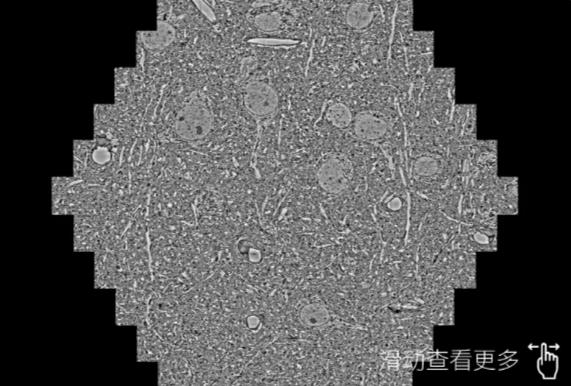

鼠脑切片。左图使用安顺蔡司安顺扫描电镜MultiSEM706对165μmx143pm面积区域成像,耗时仅需1.5秒。右图为鼠脑切片中30μm区域放大效果。样品由芝加哥大学B.Kasthuri提供。

使用蔡司高速安顺扫描电镜MultiSEM对1mm²人脑皮层组织进行高分辨成像,并对其中的各种细胞结构进行三维重构分析。左图展示了2x3mm²组织平面中锥体神经元的三维重构效果。右图显示了局部体积神经元三维重构。图像由哈佛大学chtman实验室提供,渲染图由D. Berger 制作。